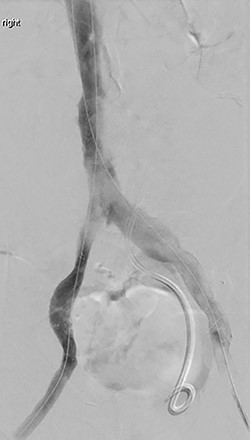

The patient was taken to the operating room immediately for percutaneous balloon angioplasty and stenting of the right EIA. The right femoral artery was accessed, and an angiogram confirmed occlusion of the right EIA. The occlusion was crossed, and an 8-mm Viabahn stent was placed to treat the occlusion. The completion angiogram showed complete revascularization of the right leg (Fig. 3). After hemostasis, the compartmental pressures of the right leg were noted to be normal, and normal Doppler signals were observed.

(A) Shows initial retrograde angiogram of right common femoral artery with occlusion at the level of the EIA. (B) demonstrates restoration of flow postangioplasty and stenting.